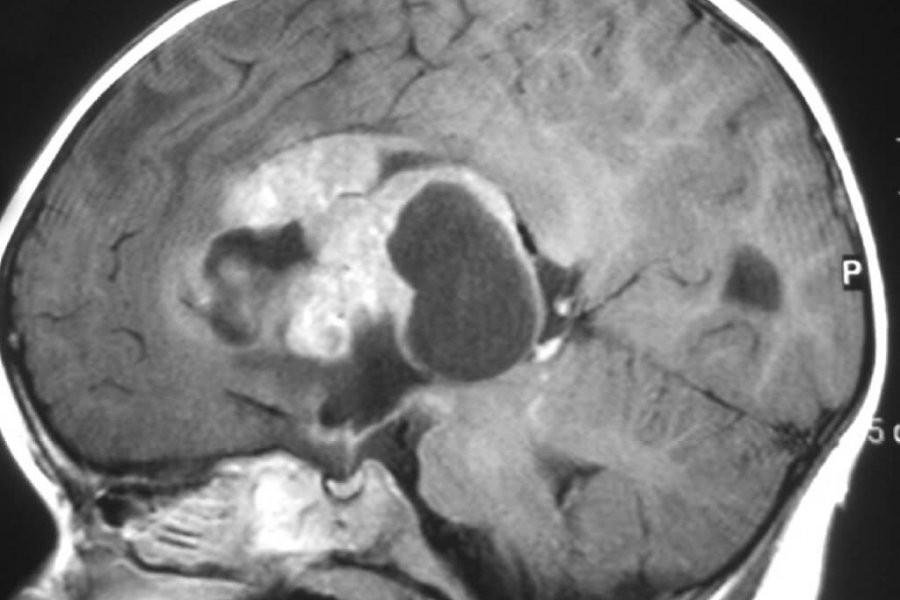

«Основными методами диагностики рака мозга являются компьютерная томография с контрастом (КТ), магнитно-резонансная томография (МРТ)», - сказал Борзяница.